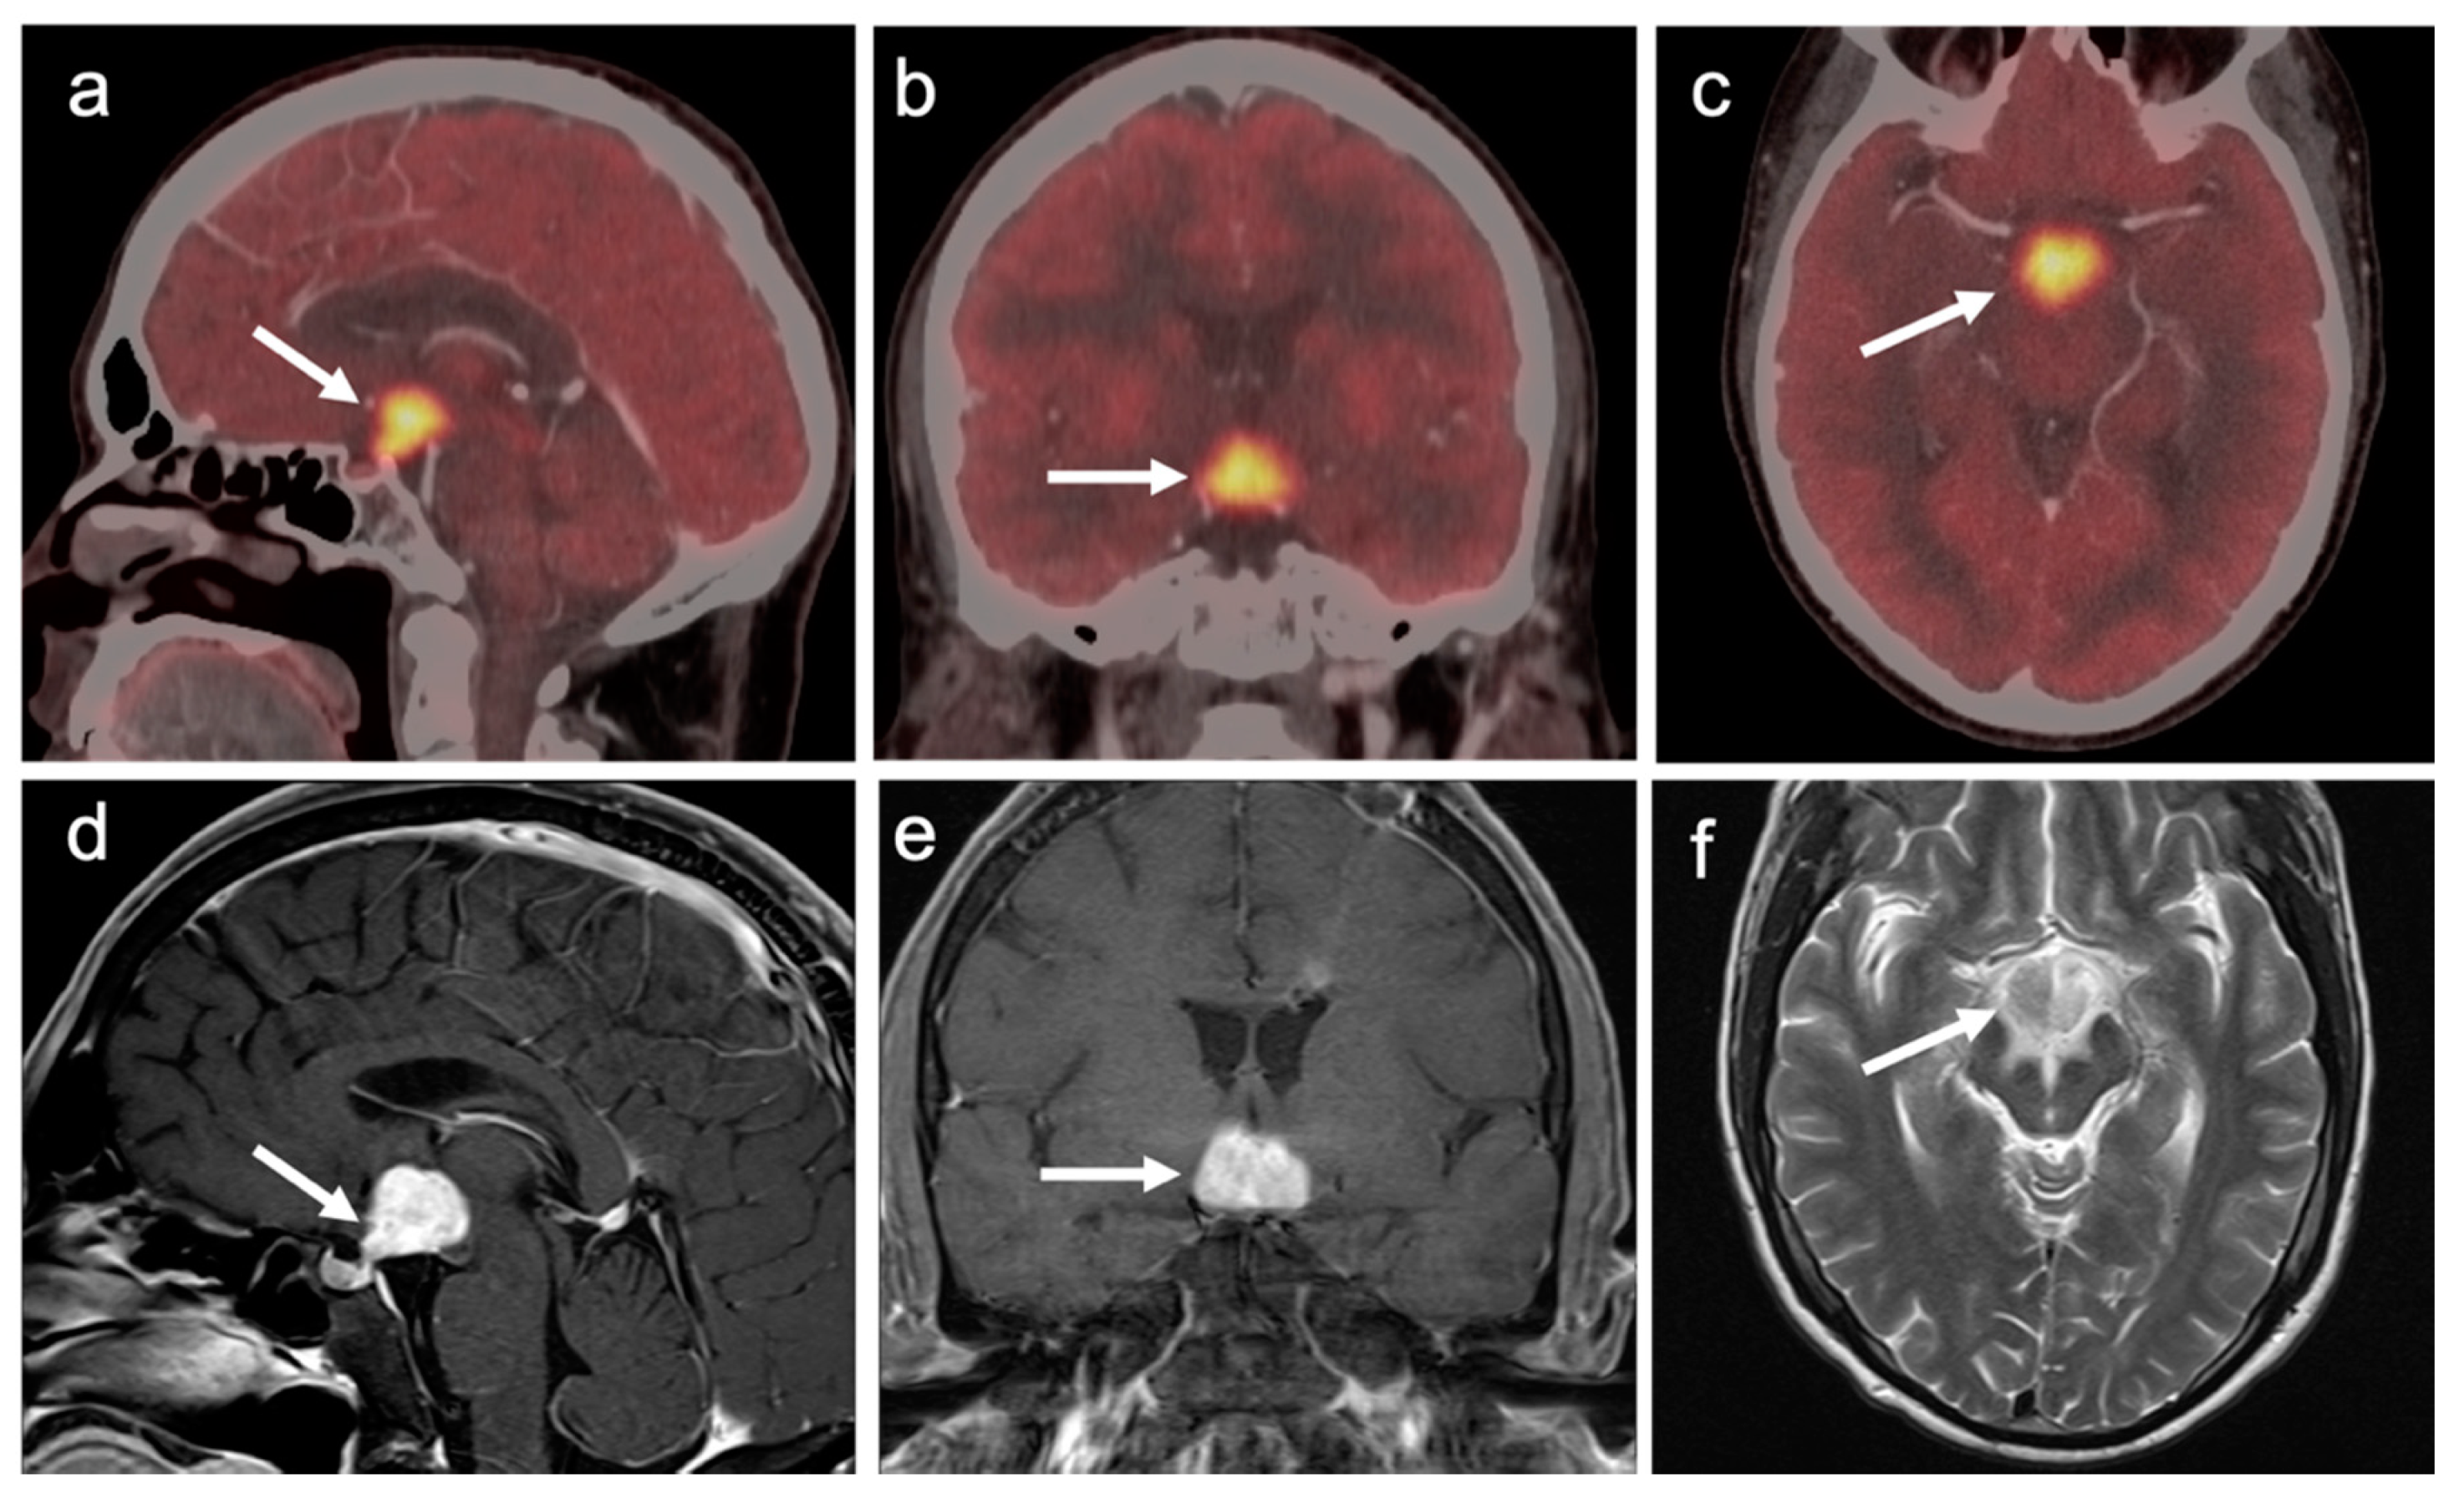

3.7. Meningioma

4. Conclusions